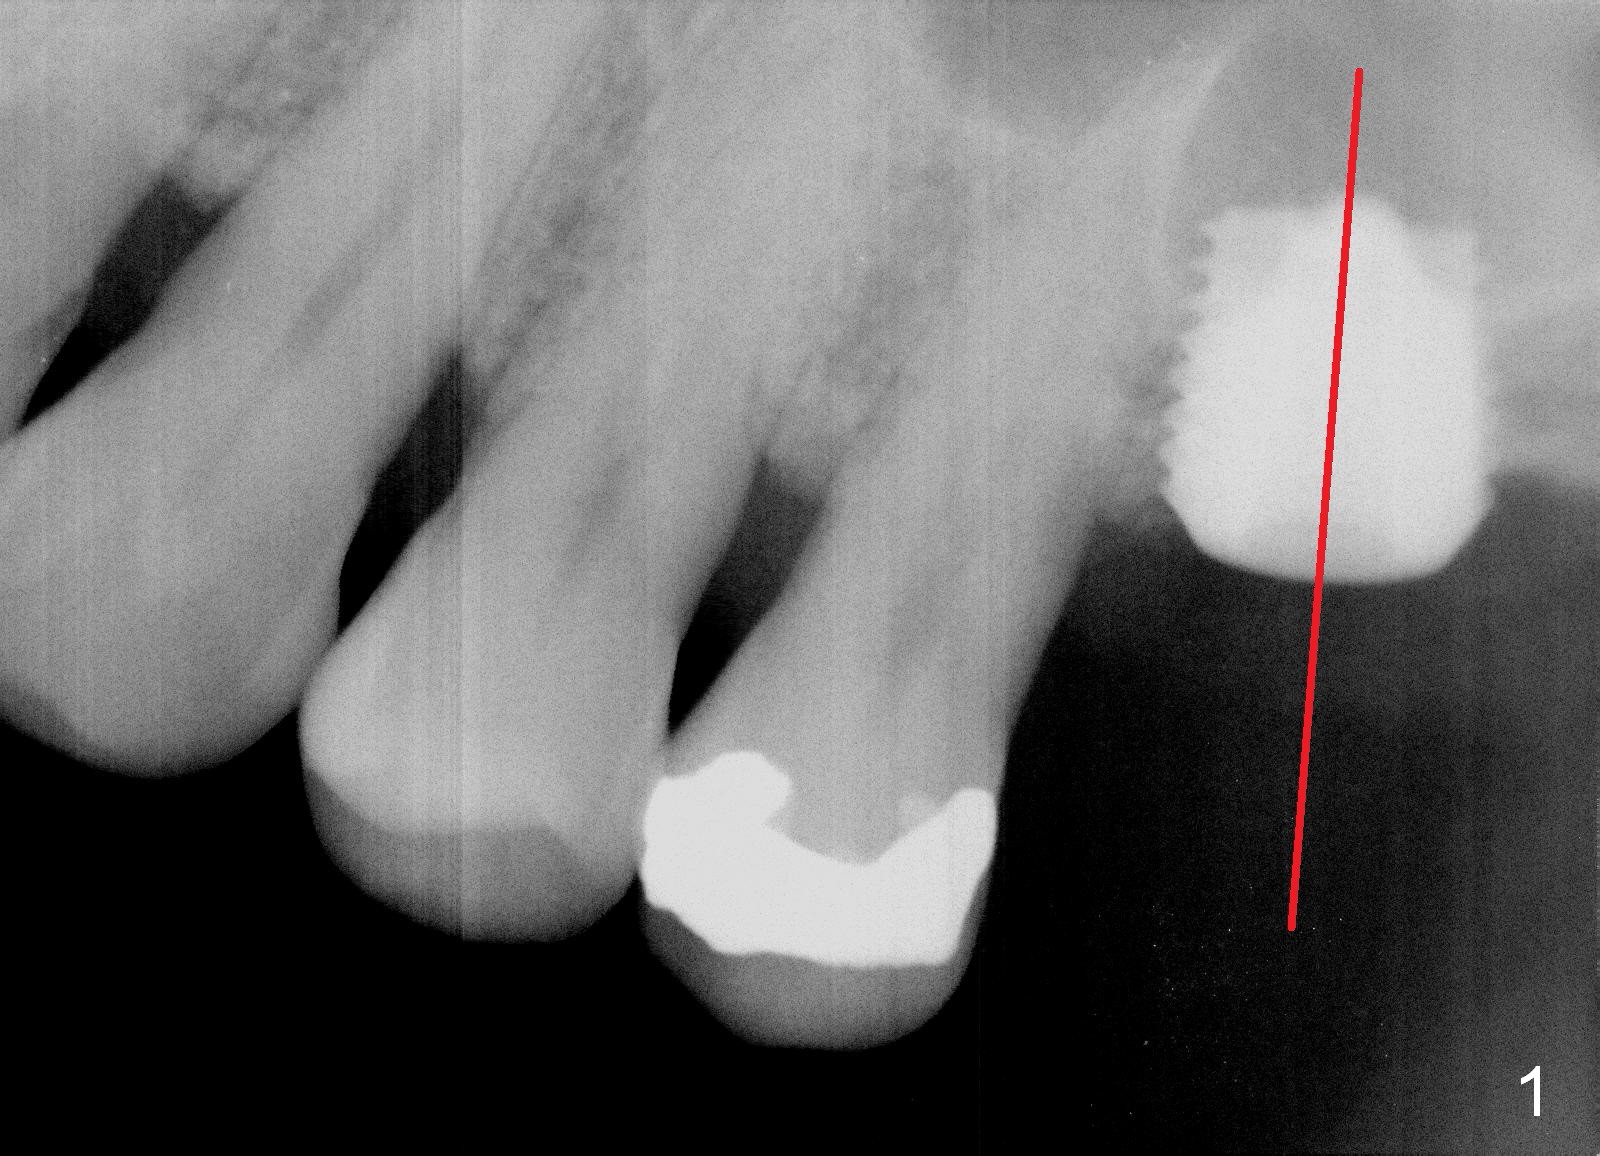

The implant recipient site is wide buccopalatally. After incision, a 3.9/4.7 mm trephine bur (from UF Extra Wide Implant kit) is used to initiate osteotomy 2.5 mm from the distal surface of the tooth #13. The depth of the trephine bur is 2 mm. The block of bone is difficult to be removed from the osteotomy. It is pushed into the sinus with a 3.5 mm osteotome with minor membrane perforation. The perforation is getting worse when allograft and Osteogen is being pushed upward. It is repaired with insertion of Osteotape and more durable collagen membrane, followed by bone graft. The osteotomy opening is enlarged slightly with a 6x6 mm tapered drill, followed by insertion of a 6.5 mm tap. When a 7x6 mm bone-level implant is placed with >60 Ncm, the axis is not parallel to that of the neighboring teeth. The implant is backed up and re-directed. The trajectory is changed within normal limit (Fig.2); the torque is slightly less than before. The distal 2nd thread is outside the crestal bone (Fig.2 <). The implant is placed deeper so that the distal 2nd thread is almost subcrestal (Fig.3). The remaining threads are covered by bone graft, followed by collagen membrane. There is tension to close the wound. A cemented abutment is placed (6.8x4(2) mm) to hold perio dressing in place. Postop instruction is given, including sinus precaution. Afrin is prescribed. The patient continues using Amoxicillin and Chlorhexidine postop. Surprisingly, there is no sinus symptom postop. The perio dressing remains in place 1 week postop (Fig.4). Later on, mild infection develops around the implant orally. One week of Amoxicillin is prescribed. The symptom improves. One month postop, the patient returns for follow up: the distal implant plateau is exposed (Fig.5 I). A provisional is fabricated for protection of the wound and comfort (Fig.6 P). The exposed plateau should be able to be covered by the gingiva in a few months.